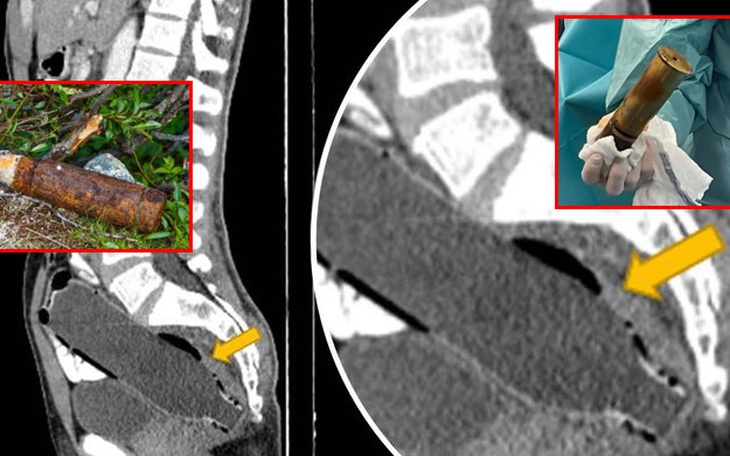

Ảnh vui 23-12: Đang yên đang lành tự dưng... Tết đến rồi!!! Ảnh vui 23-12: Đang yên đang lành tự dưng... Tết đến rồi!!! Chi 1,3 tỉ đồng làm Chi 1,3 tỉ đồng làm 'đôi cánh thiên thần' bằng tiền thật tặng người yêu Cụ ông nhập viện với quả đạn pháo trong... trực tràng Cụ ông nhập viện với quả đạn pháo trong... trực tràng